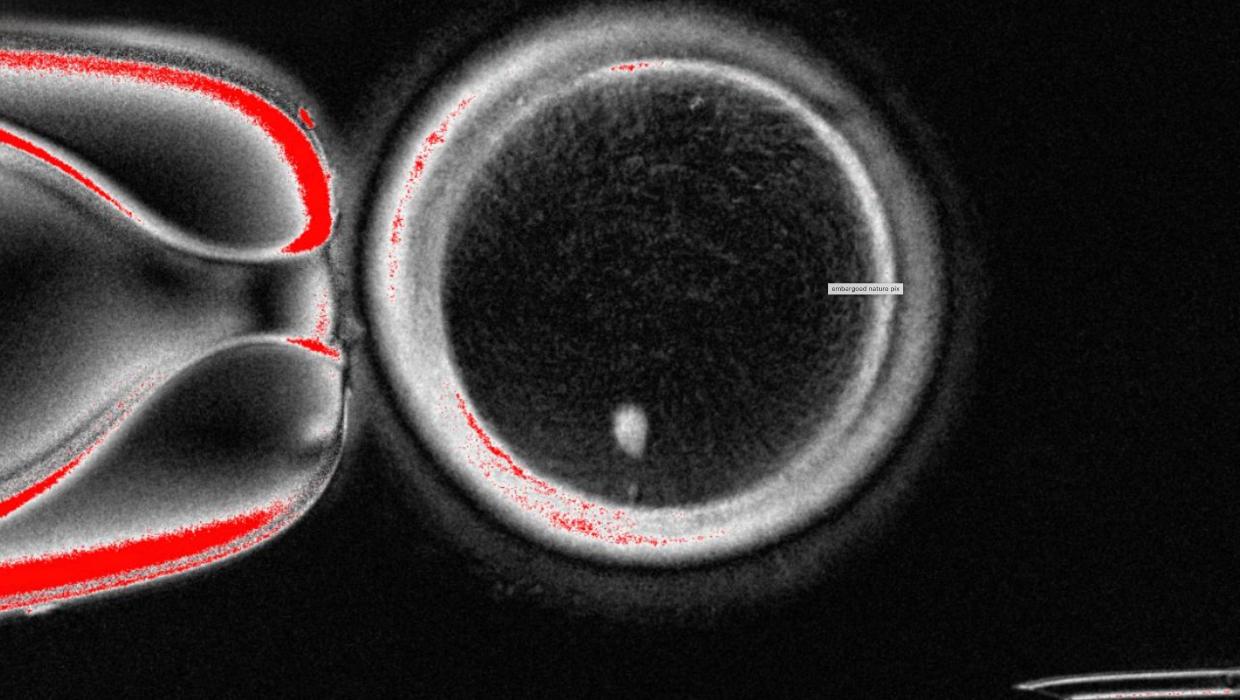

Researchers in the United States have successfully converted human skin cells into fertilizable eggs. This groundbreaking achievement represents a significant advancement in the field of reproductive medicine, potentially paving the way for lab-grown eggs and sperm to assist individuals facing fertility challenges.

This innovative research, conducted by a team at the University of California, Los Angeles (UCLA), marks a pivotal moment in efforts to create viable gametes from somatic cells. By reprogramming skin cells into pluripotent stem cells, the scientists were able to coax these cells into developing into oocytes, or egg cells, that possess the ability to be fertilized.

The researchers have successfully demonstrated that the reprogrammed skin cells can develop into functional egg cells within a laboratory setting. In their experiments, the scientists observed that these lab-grown eggs could undergo fertilization and develop into early-stage embryos, albeit in a controlled environment.